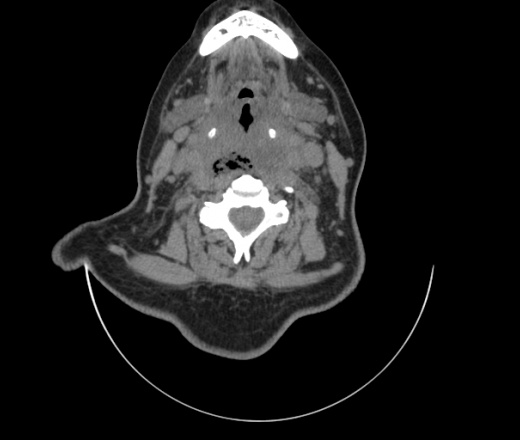

Женщина поступила в х/о спустя 4 дня после того как при употреблении карася подавилась костью.

Наличие газа в средостении на протяжении тел С2-С6 (медиастинальна эмфизема); рыбная кость на уровне тела С6.

При всем уважении, но говорить о медиастинальной эмфиземе, оценивая мягкие ткани шеи, как-то слишком резко. На мой взгляд, это ретрофарингеальное пространство.

Эвакуировали почти 100мл гноя. Но кость не смогли найти. Думаю что она даст дальнейшее ослоднение. Эндоскопически за черпалонадгортаной звязкой не смогли зайти в пищевод, все мягкие ткани отечные, просвет пищевода сдавлен. По всей видимости параэзофагеальная клетчака тоже задействована. Эмпиема, если ее можно так назвать, незнаю как правильно дошла до уровня яремной вырезки. Чем закончиться напишу. Ждем медиастинита.

Согласен с Вами; конечно, наличие газа в клетчатке ретрофарингеального пространства (затмение с опечаткой..). К сожалению, процесс "продвигается" к медиастиниту. Но почему никто, не отмечает наличие рыб. кости; или это для Всех очевидно?

Кость то мы сразу выявили, размеры где то 17*2мм, но ее так и не получается найти в этой каше